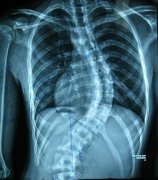

强直性脊柱炎症状

• 强直性脊柱炎都有什么的早期症状

• 强直性脊柱炎发病前的病症是哪些

• 强直性脊柱炎的晚期症状表现是什么

• 强直性脊柱炎在临床上的表现

• 强直性脊柱炎有什么样的症状体现

• 哪些表现是强直性脊柱炎的表现

• 强直性脊柱炎有什么样的发病特点

• 强直性脊柱炎会有的症状表现是哪些

• 强直性脊柱炎在晚期时会有何明显表现

• 如何来了解强直性脊柱炎发病时的表现